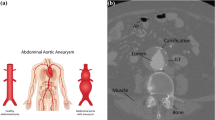

This case was a 67-year-old female patient. CT revealed an infrarenal AAA with a sharp, angled neck and a short neck. Both angle α and β were nearly 90°, and neck of the aneurysm was 12 mm approximately. The right and left renal arteries (RAs) raised at angle α. The right common iliac artery was 21 mm in length and severe tortuous, and the left was 16 mm, yet without tortuosity (Fig. 1). In this extremely challenging case, it was difficult to predict the changes in shape after the deployment of a stent. It’s known that such changes would directly affect the influx of RA and the adhesion of the struts, and both of them associates with prognosis. Thus, location and approach selection, and intervention after shape change post-deployment were extremely important; however, these factors are far difficult to manage and predict in common methods, e.g., CT in the case.